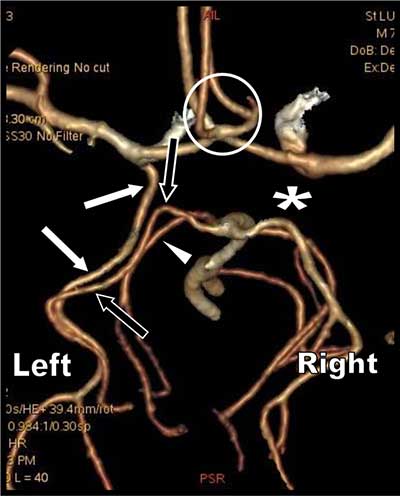

Figure 1

3D volume rendering view of the Circle of Willis obtained from the CT arterial phase. View from the vertex (left side is thus on the right of the figure).